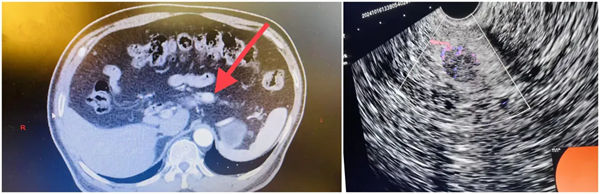

近日,寶雞市人民醫院肝膽胰脾外科成功完成兩例經超聲內鏡引導下胰腺腫瘤無水乙醇消融術,術后患者恢復良好。

62歲的李女士反復出現腹脹、頭暈、心慌,曾在多家醫院就診,但一直未有明確診斷,后就診于市人民醫院肝膽胰脾外科,完善檢查后診斷為胰島細胞瘤。治療胰島細胞瘤的傳統方式是外科手術切除,但這兩名患者腫瘤位于胰腺實質內,定位困難,無法進行精準瘤體剔除,需要進行胰十二指腸切除或胰體尾切除術。但外科手術存在創傷大、恢復慢、并發癥多等缺點。

經過多次討論,評估患者各項檢查后,肝膽胰脾外科治療團隊綜合評估,考慮患者及家屬意見后,決定采用先進的超微創技術——超聲內鏡引導下瘤內無水酒精注射消融術進行瘤體精準治療。

超聲內鏡引導下胰腺神經內分泌腫瘤無水乙醇消融術依托先進的超聲內鏡設備,精準定位腫瘤位置,通過極細的穿刺針將無水乙醇直接注入腫瘤內部。無水乙醇能夠使腫瘤細胞迅速脫水、凝固,進而壞死,達到消除腫瘤的目的。